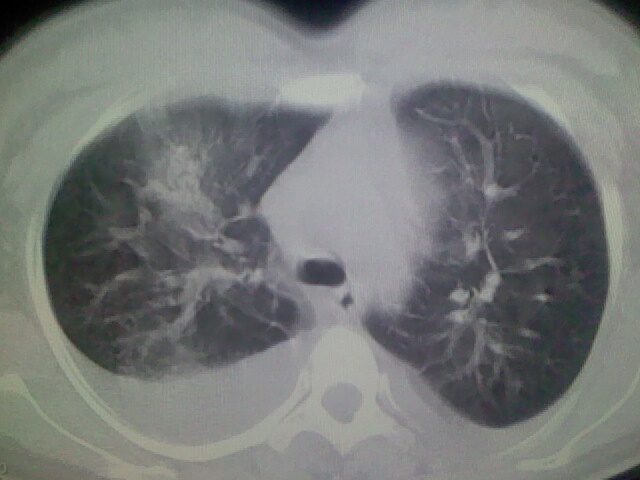

女,24,剖腹产后,突觉胸痛,干咳,不能平卧

双肺“肺泡性肺水肿” “胸腔积液”!

考虑肺梗塞、肺水肿,双侧胸腔积液

全心衰导致积液、肺水肿。不知手术前有无心脏病变?

临床资料及影象表现支持围产期扩张型心肌病改变,心衰。

考虑产后心肌病,心功能不全,肺水肿,双侧胸腔积液。

考虑产后心肌病,心功能不全,肺水肿,双侧胸腔积液。不排除羊水栓塞可能。